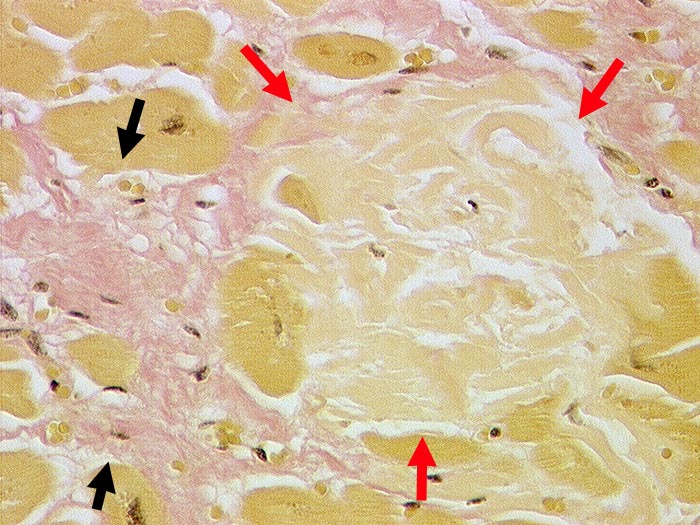

Myokardamyloidose

Systemerkrankung/Immunpathologie

Kardiovaskuläres System

Herz links